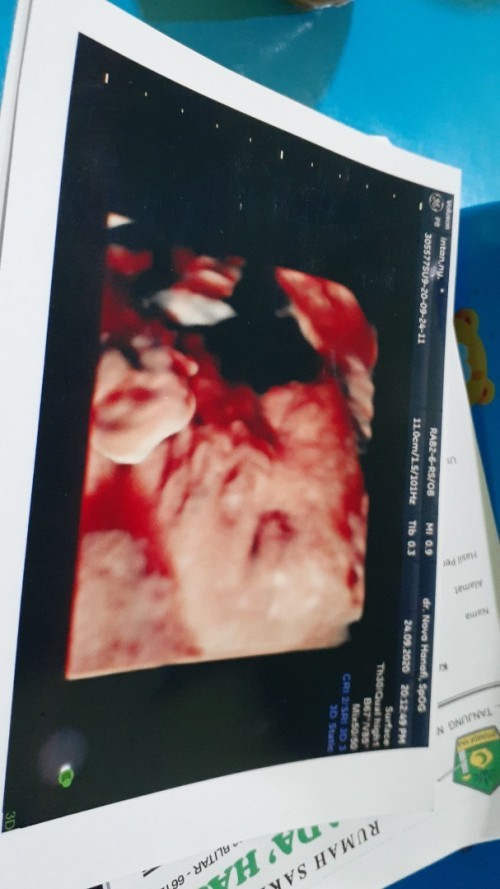

Ini waktu 27 weeks, sekarang udah 31 weeks blm USG lagi 😁